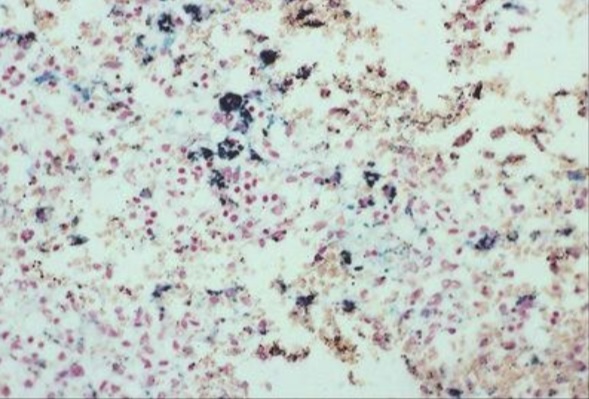

Anthracosis

Asbestosis

Chalicosis

Pneumoconiosis

Silicosis